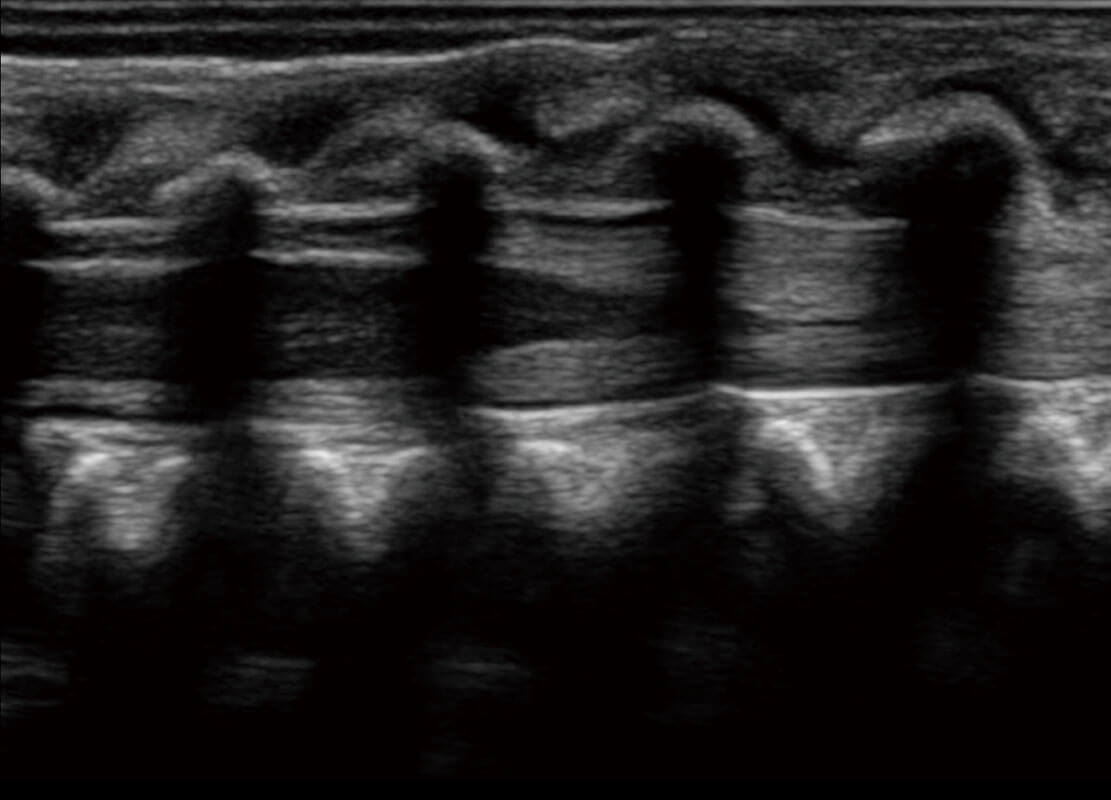

P60搭载一系列胎儿心脏成像技术,实现精细的胎儿心脏评估。

四腔切面

四腔心血流

右室双出口

胎心容积成像